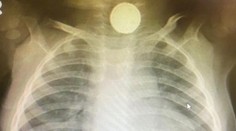

Murcia Lekár si myslel, že chlapec (1) má covid. Nesprávna diagnóza pre neho skončila doživotnými následkami Róbert Ďurkáč 25. 2. 2021